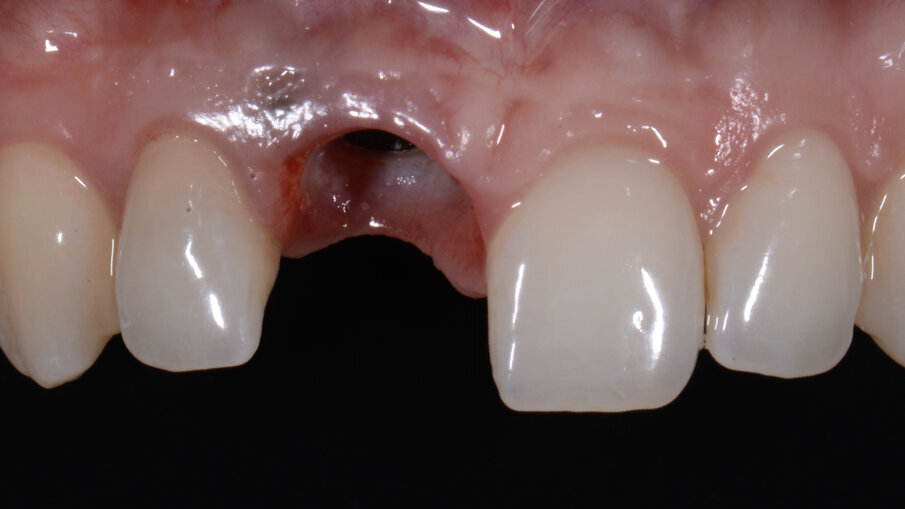

In seguito ad un riassorbimento radicolare esterno, una giovane paziente di 28 anni danneggia irreversibilmente il dente 1.1. È presente una fistola vestibolare e la sequenza radiografica mostrava un progressivo danno a carico della radice con coinvolgimento del tronco radicolare e del terzo cervicale del dente (Figg. 2-5).

Figg. 2-4_Immagini iniziali.

- Creazione della “Maschera gengivale”

Trascorsi quattro mesi, ad avvenuta osteointegrazione dell’impianto, il condizionamento dei tessuti appariva ottimale sia in termini di qualità dei tessuti sia in termini di volume rigenerato. I profili gengivali erano perfettamente armonici e naturali grazie al provvisorio (Fig. 29). A questo punto, dopo avere svitato il provvisorio dall’impianto, ho copiato con lo scanner intra-orale la posizione delle papille e della parabola gengivale. In tal modo, creando la cosiddetta “Maschera gengivale”, ho condiviso con il software le informazioni morfologiche necessarie per realizzare i manufatti protesici definitivi (Figg. 30, 31).